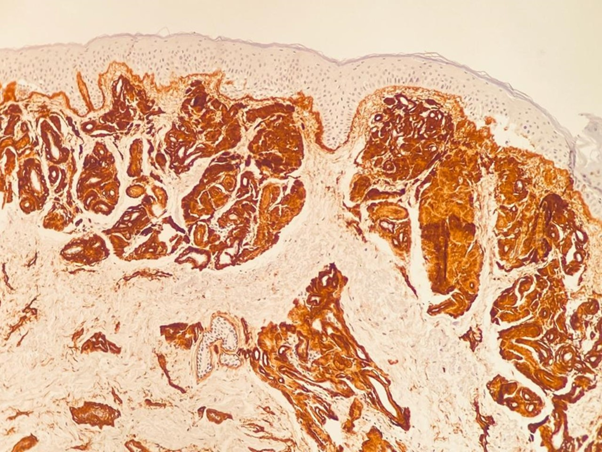

Porphyria was our main hypothesis, although porphyrins urine test was negative and no fluorescence was detected on the urine. Subsequently, a skin biopsy was performed, which revealed hyaline deposits in the papillary dermis and around the vessels that became more evident on Periodic Acid-Schiff (PAS) stain with diastase (Figure 3 & Figure 4). Immunohistochemistry was also performed, and revealed positivity for type IV collagen (Figure 5).

Figure 4 Hyaline deposits in the papillary dermis and around the vessels that became more evident on Periodic Acid-Schiff (PAS) stain with diastase.